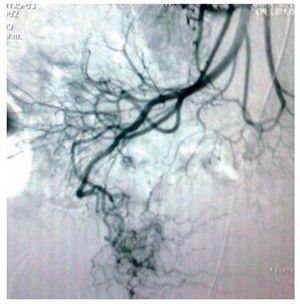

Mujer de 47 años, diabética e hipertensa de larga evolución, con antecedente de nefrectomía derecha por donación cinco años antes. Su padecimiento se inició a fines de 2008 con presencia de evacuaciones hematoquézicas y melena, por lo que requirió múltiples transfusiones. La endoscopia alta y colonoscopia no detectaron el sitio de hemorragia. En agosto de 2009 presentó choque hipovolémico secunadario a hematoquezia (hemoglobina de 3.5 g/dL) que requirió de transfusión de siete paquetes globulares. Se realizaron nuevamente endoscopia alta y colonoscopia que no detectaron en sitio de hemorragia. El gammagrama con eritrocitos marcados mostró concentración anormal del radioisótopo en la flexura hepática. Una enteroscopia no mostró sangrado evidente. Se practicó una angiografía selectiva de arteria mesentérica superior (AMS) en fase arterial (Figura 1), que mostró vasos de neoformación tortuosos e irregulares a nivel de íleon, sin retorno venoso temprano. La angio-tomografía computarizada (angioTC) con reconstrucción coronal y proyección de máxima intensidad (Figura 2), detectó una imagen hipodensa, con vasos tortuosos de neoformación que nacían de la AMS. La angioTC en 3D (Figura 3) reveló múltiples vasos de neoformación dependientes de la AMS localizados en íleon que demuestran una tumoración con gran vascularidad. Se realizó laparotomía exploradora encontrando un tumor a 90 cm de la válvula ileocecal (Figura 4). El análisis histopatológico determinó tumor estromal de alto grado con bordes quirúrgicos libres de lesión, con inmunohistoquímica para CD117 (Figura 5) y S100 positivos.

¿ Figura 1. Angiografía selectiva de arteria mesentérica superior en fase arterial. Se aprecian vasos de neoformación tortuosos e irregulares a nivel de íleon, sin retorno venoso temprano.